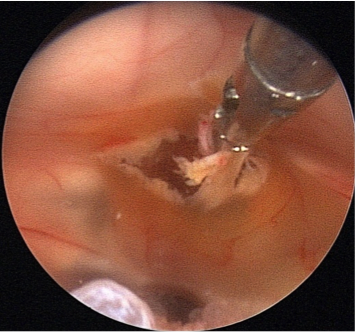

Bei dem Endoskop handelt es sich um ein optisches Lichtleitungssystem, an das eine Kamera angeschlossen ist. Darüber hinaus ist es mit einem Spül- und Arbeitskanal zum Einbringen von Miniaturinstrumenten wie Fasszangen, Ultraschallsonden oder Ballonkathetern ausgestattet.  Der Operationszugang ist über einen bleistiftdünnen Kanal möglich. Die Kamera ermöglicht es, gestochen scharfe Bilder in Full-HD-Qualität aus verschiedenen Perspektiven auf einen hoch auflösenden Bildschirm zu übertragen. Verschiedene Winkeloptiken ermöglichen die umfassende Inspektion aller Bereiche. Das verschafft dem Operateur einen detailreichen Blick auf das Operationsfeld mit seinen empfindlichen Strukturen wie Blutgefäßen oder Nerven, wodurch die Operationssicherheit gesteigert wird.

Uns stehen drei Endoskopie-Systeme zur Verfügung. Eines dient der transventrikulären Endoskopie. Dieses Instrument wird durch den Ventrikel (Nervenwasserkammer) eingeführt und zur Entfernung von Tumoren, zur Herstellung von Verbindungen innerhalb der Nervenwasserkammer und zu den Räumen außerhalb des Gehirnes, aber auch zur Probeentnahme von Tumoren, die neben der Mittellinie liegen, genutzt.

Tumoren und Zysten in den Hirnkammern können über ein kleines Bohrloch im Schädel so oft sicher und schonend entfernt werden. In Kombination mit modernster Neuronavigation und intraoperativer Bildgebung kann sich der Chirurg genau im OP-Gebiet orientieren und das Endoskop exakt positionieren. Das sind optimale Voraussetzungen für die Behandlung hochkomplexer Erkrankungen.